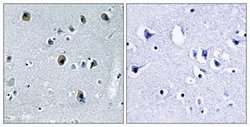

Immunohistochemistry

ABIN1534360 IHC